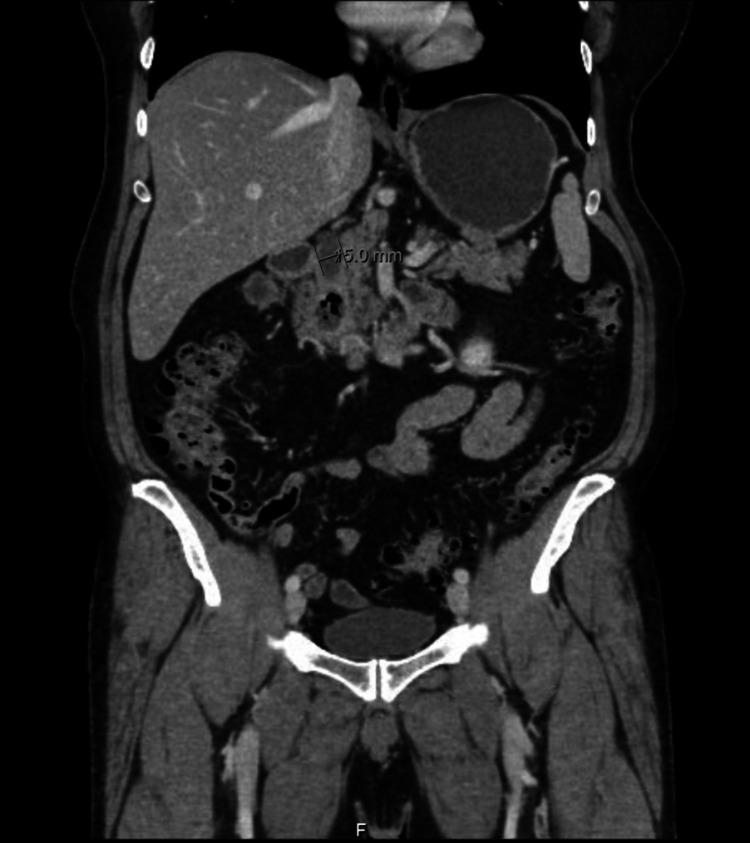

Lemmel syndrome is a rare cholestatic disease caused by a periampullary duodenal diverticulum (PAD) compressing the common bile duct (CBD) or pancreatic duct, which results in acute abdominal pain and/or obstructive jaundice in the absence of other pathology explaining the symptoms. It can be easily misdiagnosed unless carefully detected by abdominal ultrasound (US), barium studies, computed tomography (CT) scan, esophagogastroduodenoscopy (EGD), magnetic resonance cholangiopancreatography (MRCP), and endoscopic retrograde cholangiography (ERCP), which is also the treatment modality of choice. We herein report a case of a 62-year-old male presenting with prolonged hypochondrial pain. He was diagnosed with Lemmel syndrome after performing US, barium meal, CT scan, EGD, and MRCP that was managed successfully by ERCP with sphincterotomy and stent placement.

莱姆尔综合征是一种罕见的胆汁淤积性疾病,由壶腹周围十二指肠憩室(PAD)压迫胆总管(CBD)或胰管引起,在没有其他能解释症状的病理情况下,会导致急性腹痛和/或梗阻性黄疸。除非通过腹部超声(US)、钡剂造影、计算机断层扫描(CT)、食管胃十二指肠镜检查(EGD)、磁共振胰胆管造影(MRCP)和内镜逆行胰胆管造影(ERCP)仔细检测,否则很容易误诊,而ERCP也是首选的治疗方式。我们在此报告一例62岁男性,表现为长期季肋部疼痛。在进行了超声、钡餐、CT扫描、EGD和MRCP检查后,他被诊断为莱姆尔综合征,并通过ERCP行括约肌切开术和支架置入术成功治疗。